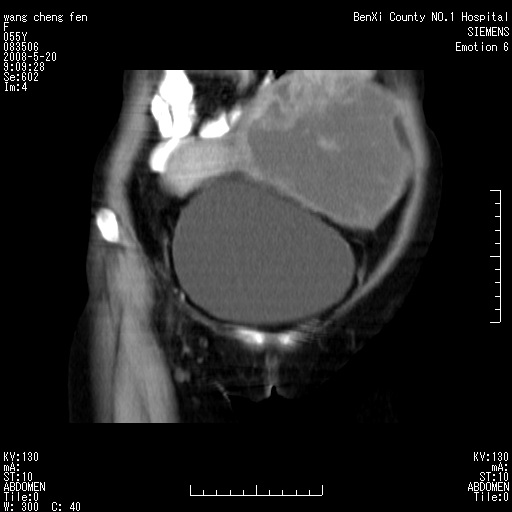

女、绝经后阴道流血3个月

左侧附件区巨大囊实性病灶,边缘光整,病灶囊壁较厚,增强示囊壁及实性部分明显强化,强化呈度与宫体实质大致相同,宫腔积液征像,未见盆腔积液等其他异常,考虑左侧卵巢囊腺癌,不除外囊腺瘤及浆膜下肌瘤坏死

左侧附件区巨大囊实性病灶,边缘光整,病灶囊壁较厚,增强示囊壁及实性部分明显强化,强化呈度与宫体实质大致相同,宫腔积液征像,未见盆腔积液等其他异常。绝经后阴道流血3个月,结合病史左侧卵巢囊腺癌首先考虑,宫腔扩大不除外累及。期待结果。

支持浆膜下子宫肌瘤.之前由于网络原因未看全图片,现在重看,宫颈见一类圆形低密度影,增强轻度强化,低于肌层强化,宫腔扩大,考虑宫颈癌伴宫腔积液可能性大.

囊实性肿块分隔厚度较大,厚薄不均,增强实性成分明显强化,有不规则阴道流血,卵巢囊腺癌可能性大。

1,宫颈部占位,宫颈癌?2,左侧附件区囊实性占位,界较清,实质部分强化明显。考虑浆膜下或阔韧带肌瘤囊变可能大。囊腺类肿瘤不除外。